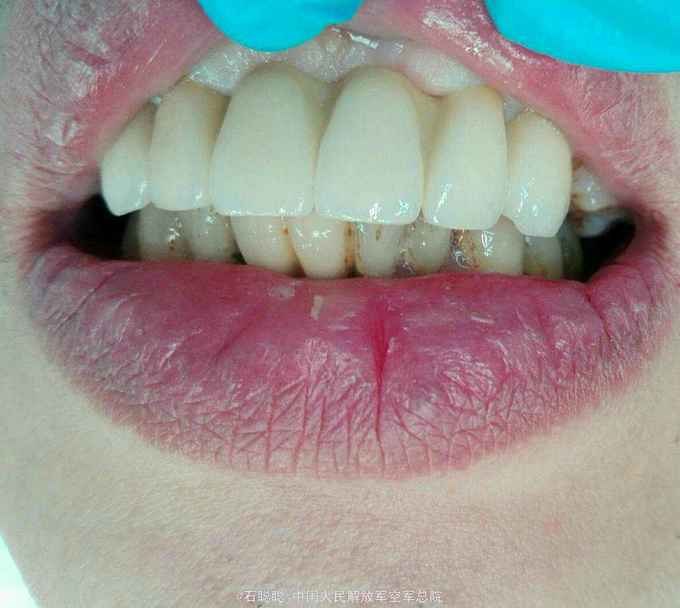

诊断:11、21缺失 治疗计划:向患者交代种植、活动、固定义齿修复方案的优缺点,患者考虑到种植周期长、活动修复难以满足美观要求,选择全瓷固定桥修复方案,但患者12、22基牙条件不甚理想,交代患者修复后要严密观察,定期复诊。 处置:12、13、22、23碧蓝局麻下开髓,拔髓,冲洗,置失活剂,氧化锌暂封 一周后复诊:去除暂封,测量根长,12=22=19mm,扩大至25#,13=23=24mm,扩大至35#,大量冲洗,干燥根管,置CP棉球,氧化锌暂封。 一周复诊:12、13、22、23去除暂封,试主尖,冲洗,干燥,冷测压充填,拍摄根尖片,恰填,置干棉球,氧化锌暂封 一周后复诊:12、13、22、23无不适,去除暂封,磷酸锌垫底,树脂充填,预备牙体,排龈,聚醚取模制作临时冠,调磨粘固 一周后复诊:试戴内冠,就位顺利,边缘密合 一周复诊:试戴全瓷桥,由于边缘密合,固位良好,调节正中咬合、前伸咬合、侧方咬合为轻接触,磨光U200粘固

讨论:在这个病历中,由于12、22牙槽骨有所吸收,并且缺牙区牙槽骨有一定量的丧失,这种修复方式并不推荐,但患者了解各种修复方式优缺点之后,强烈反对种植和活动修复,只能进行固定桥修复,治疗结束后除外嘱咐患者常规义齿戴总注意事项,一定要定期复查,观察基牙情况,防止牙槽骨进一步吸收。在制作义齿时,加工厂为补充缺牙区的牙槽骨吸收,龈端唇舌侧均补充了较多的瓷,可能会使得义齿视觉上比较大,这也是一种折中的做法。